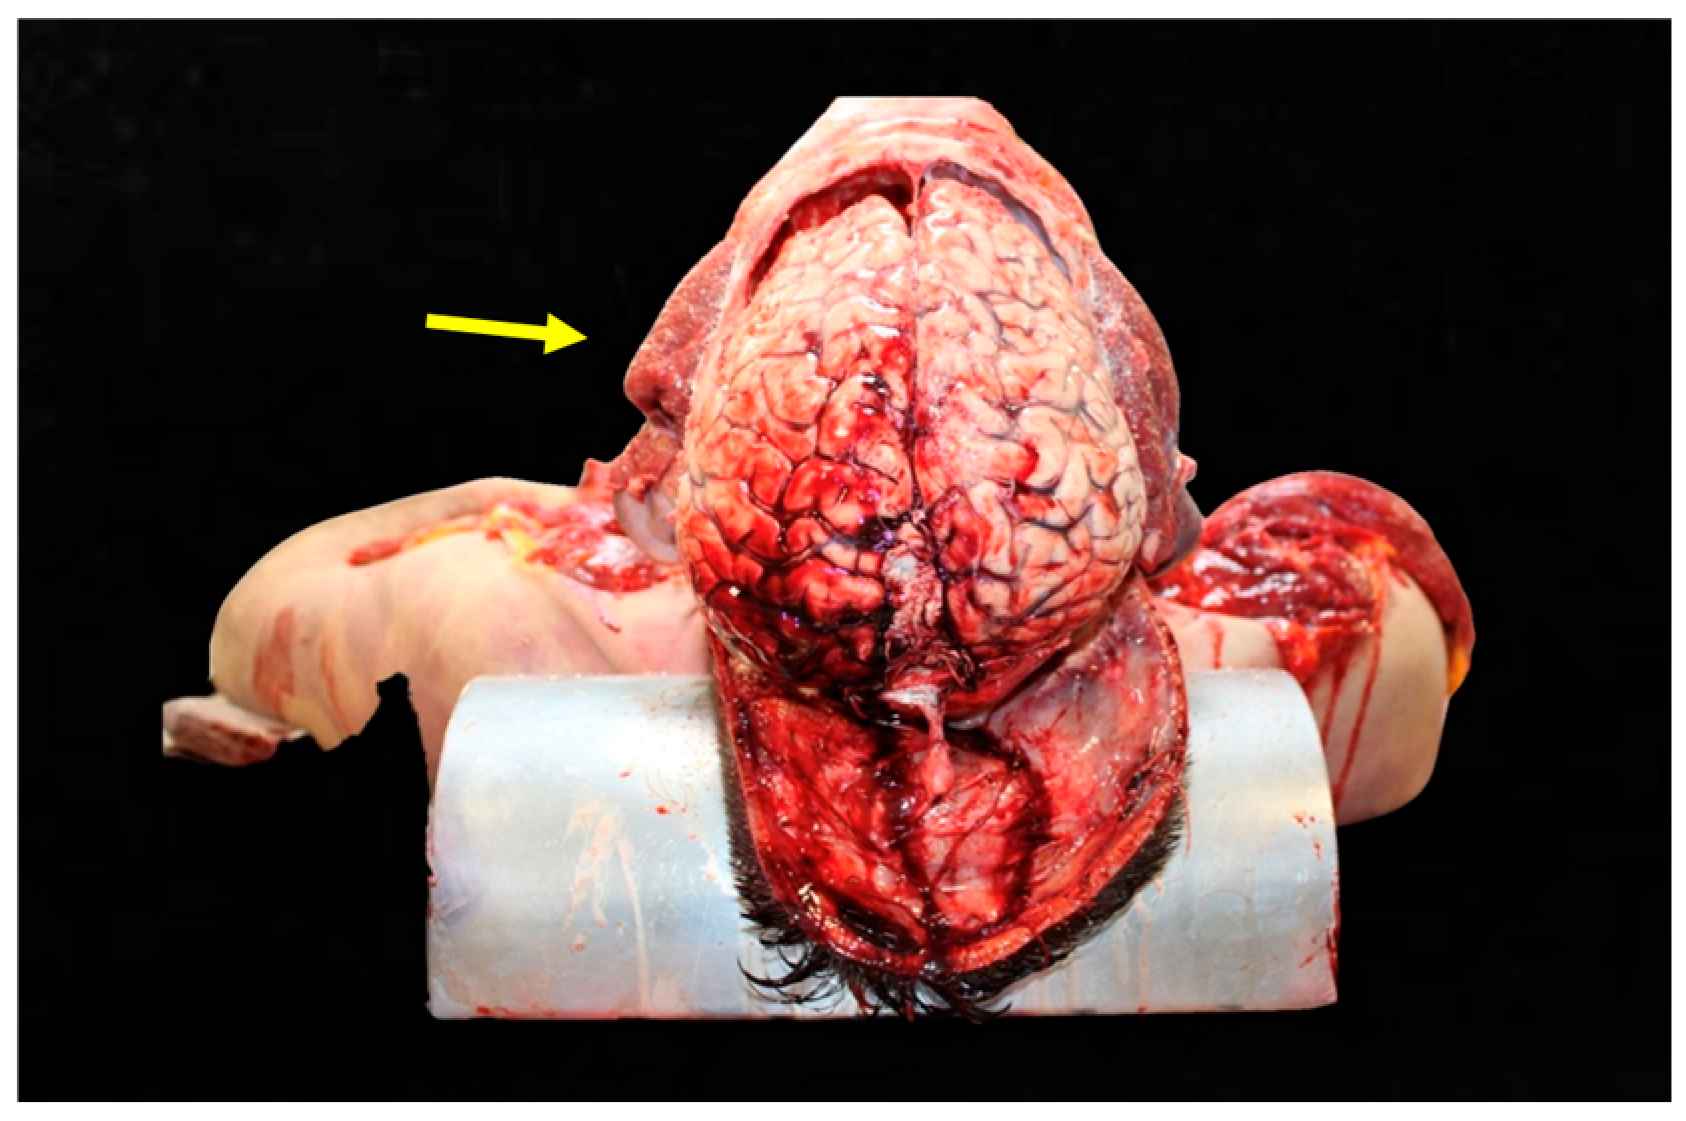

Figure 3. Trauma of the left parietotemporal region. The illustration shows localized contusions and fractures in the left parietotemporal region, correlating with lateral impacts.